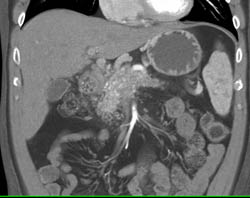

Metastatic Colon Cancer